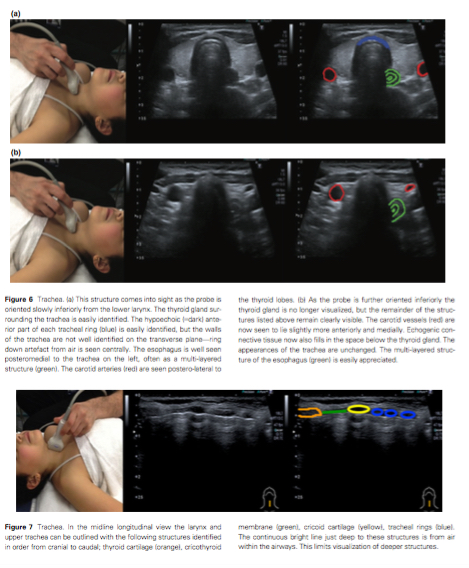

What would be really good of course is to know more about the airway before you get there with the plastic snorkel. A CT scan will always take time and a transfer. Could this be a point where ultrasound comes to the fore? After all, if you can see where the level of an injury is, that might alter your plans.

Well people are trying that. There’s at least this paper out there and it has a pretty comprehensive look at sonoanatomy and potential uses. It also says that you shouldn’t consider ultrasound in the unanticipated difficult airway.

Let’s never forget that the images in a journal article on ultrasound almost always have pictures better than you’ll probably ever manage.

This isn’t entirely an unanticipated difficult airway though. It’s not hard to foresee a world where you use your ultrasound to get a sense of the anatomy. So perhaps it’s time we started training in this in paeds anaesthesia. Once familiar with airway ultrasound you could take the time to mark the level of key landmarks like the thyroid and cricoid cartilages, the cricothyroid membrane and those first tracheal rings.

It might also be useful is in excluding other serious things. Are you trying to figure out if there is a pneumothorax or something else leading to the poor oxygenation? An ultrasound will probably give you the answers you seek. Do you want to double check the carotid arteries? There’s a probe for that too.

For now though there’s not a lot of work to recommend an ultrasound machine because it’s early days. For now maybe it should be seen but not heard whirring into action unless you’re really clear what you want to ask of it and you’ve spent the time learning the skills. It’s not the mainstay here.